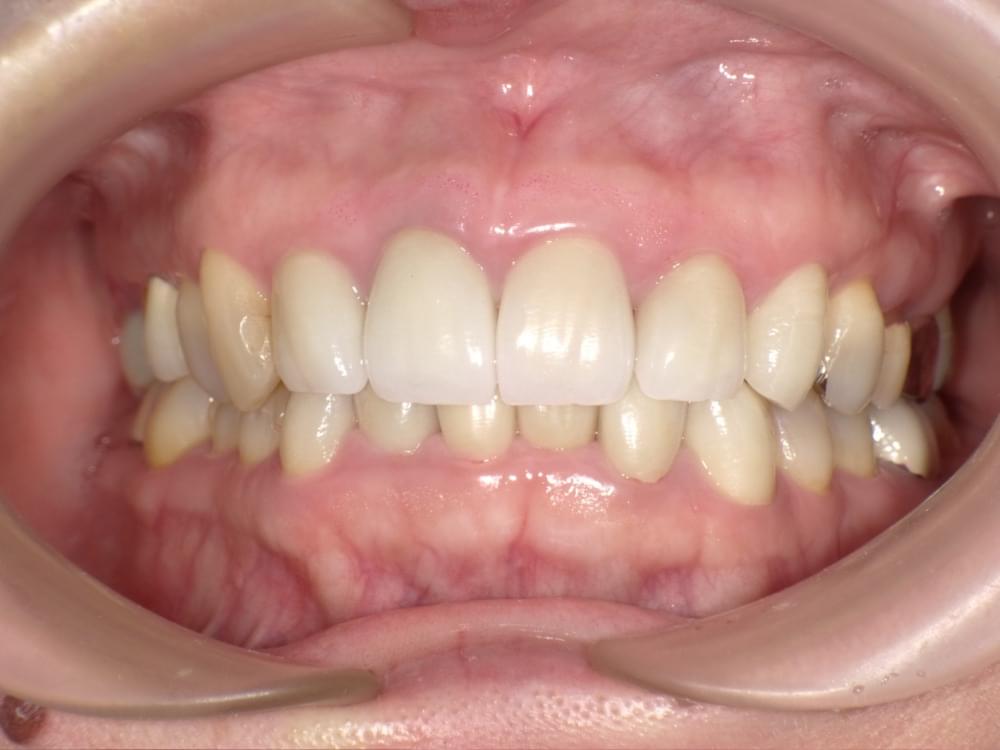

歯周病治療プログラムの治療例1

治療の概要

治療内容

行動科学に基づき、「自分の歯は自分で守る」という意識改革や行動変容を促しながら、スケーリングや歯ブラシ・フロス指導を行いました。

治療期間・回数・時間

1.5ヶ月・5回・計5時間

費用

29,500円+税

リスク・副作用

歯肉の痛み・出血